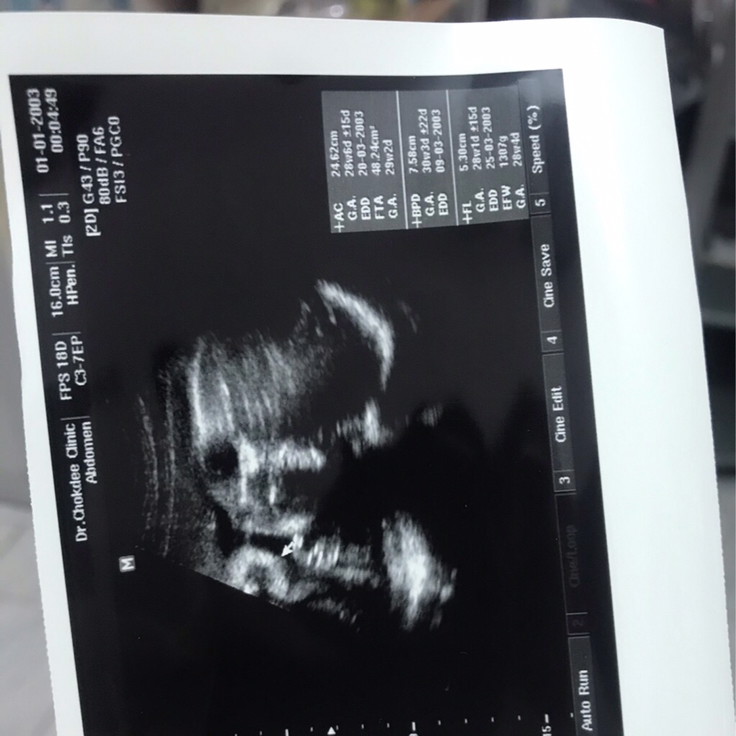

บ้านนี้ตอน 30 week ค่ะ ลุ้นตอนออกมาเหมือนกันค่ะ ดั้งจะหายมั้ย 😄

ลูกชายบ้านนี้ 26w ครับผม รอลุ้นว่า ออกมาจมูกจะโด่งมั้ยครับ

บ้านนี้ซาวตอน15 วีค ได้พ่อมาเต็มแต่รอลุ้นตอนคลอดอีกที❤️❤️

บ้านนี้ก็ซาวออกมาโด่งเหมือนพ่อ แต่รอลุ้นตอนคลอดอีกที